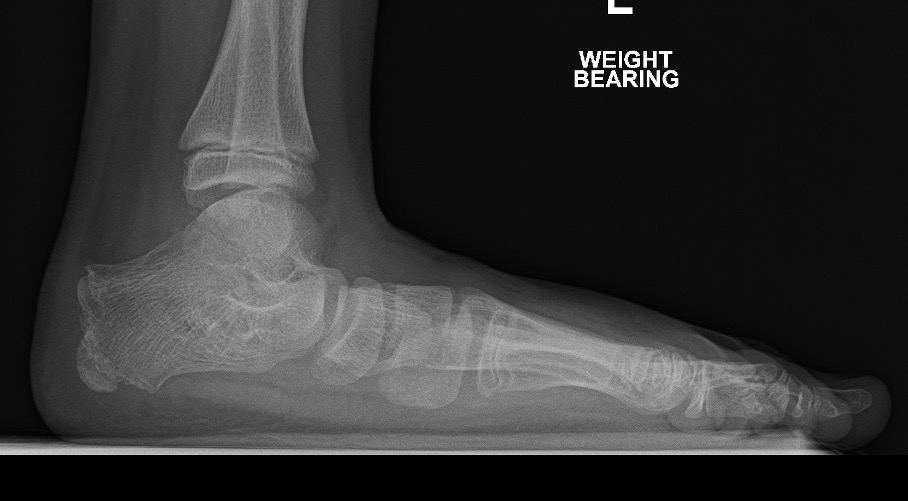

X-ray

Flatfoot

Meary's angle

- Talus - first metatarsal angle

- lateral weight bearing view

T post

Cobey's

- hindfoot alignment view

- foot plantarflexed over a block

- see that calcaneum is under the fibula not tibia